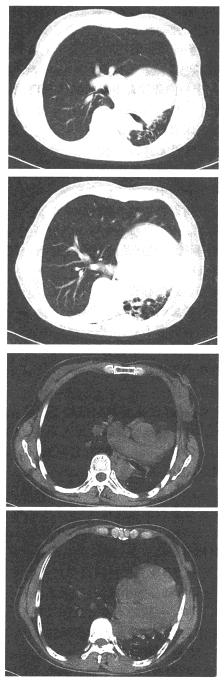

80、单项选择题

男,58岁,头痛、恶心、行走不稳,肺和脑CT检查如图,最可能的诊断为()

A.星形细胞瘤

B.脑脓肿

C.肺癌脑转移

D.脑膜瘤

E.脑梗死